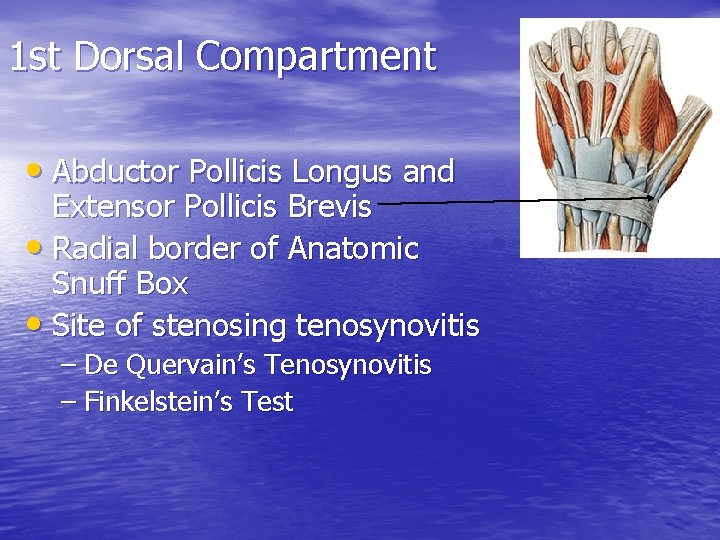

1 st Dorsal Compartment • Abductor Pollicis Longus and Extensor Pollicis Brevis • Radial border of Anatomic Snuff Box • Site of stenosing tenosynovitis – De Quervain’s Tenosynovitis – Finkelstein’s Test